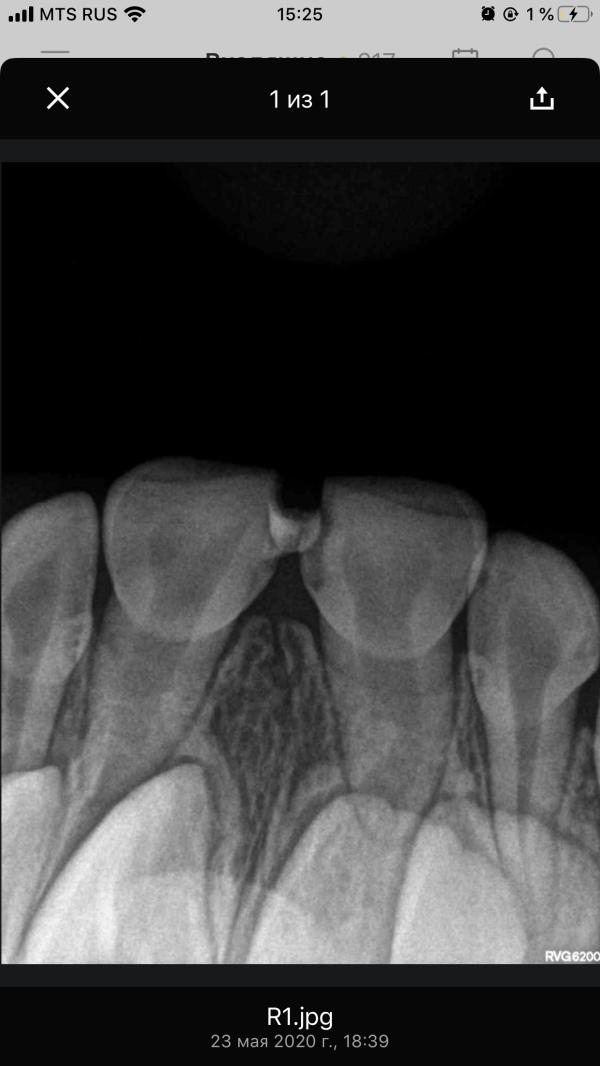

На следующий день поехали в другую клинику «Вероника». Там сделали рентген(к слову в «Зубной фее» его не делали вообще ни разу) и сделали анестезию.

4. Рентген в «Веронике» перед лечением.